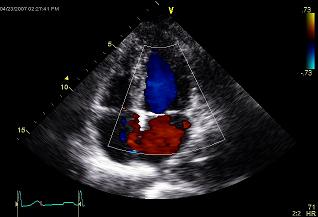

Lotulelei was held out of position workouts at the Combine last month after an echocardiogram showed his heart wasn’t pumping normally. His ejection fraction, a measure of how efficiently the heart is pumping, was reportedly 44% (cardiologists consider a heart pumping with an efficiency of 55-70% to be healthy). A source in Indianapolis told Mike Garafolo that it was hoped that Lotulelei’s low EF was related to dehydration, weight loss and/or a high sodium diet while training.

People with an ejection fraction of 44% may not be symptomatic (e.g. easily fatigued, short of breath, difficulty sleeping). Many people won’t have symptoms of a failing heart until their ejection fraction is below 35-40%. It’s also known that some athletes with healthy hearts have a low normal ejection fraction (in the 50-55% range) when they’re at rest. Additional testing and comparisons to previous studies (both before, if available, and after the February result) could shed light on those issues. But it’s also possible that teams won’t have a clear answer on Lotulelei’s health by draft day. If this scenario plays out, teams will have a hard time clearing Lotulelei to play and will certainly struggle to invest a high draft pick in a player whose long term health remains in question.